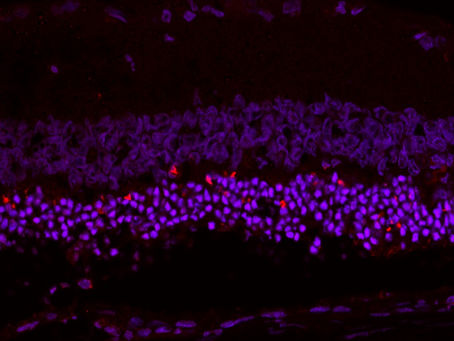

Publication: Photoreceptor Survival Is Regulated by GSTO1-1 in the Degenerating Retina

Authors: Fernando N*, Wooff Y*, Aggio-Bruce, Chu-Tan J, Jiao H, Dietrich C, Rutar M, Rooke M, Menon D, Eells JT, Valter K, Board PG,...

Riccardo Natoli